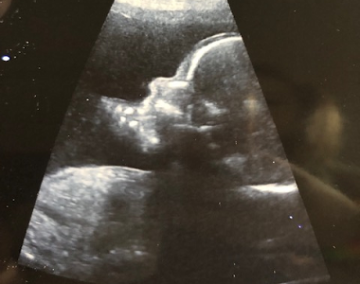

Těhotenství na Pavle v 17. týdnu už začíná být pomalu vidět

Pavla (17. týden těhotenství)

jsem v 17+1 týdnu těhotenství a mám pocit, že na mně těhotenství už pomalu začíná být vidět.

Mazání rostoucího bříška olejem Weleda proti striím s partnerem se stalo krásným večerním rituálem. Vitamíny Mamavit užívám pravidelně každé ráno a doufám (asi tak jako všechny nastávající maminky), že bude miminko zdravé. Měsíc mezi kontrolami mi přijde příliš dlouhý, a jelikož ještě necítím pohyby miminka, jsem z toho trochu nervózní. Poslední dobou mám velmi živé sny. Zdálo se mi, že to bude holčička. I dcera by si přála sestřičku, tak jsem zvědavá, jak to nakonec dopadne.